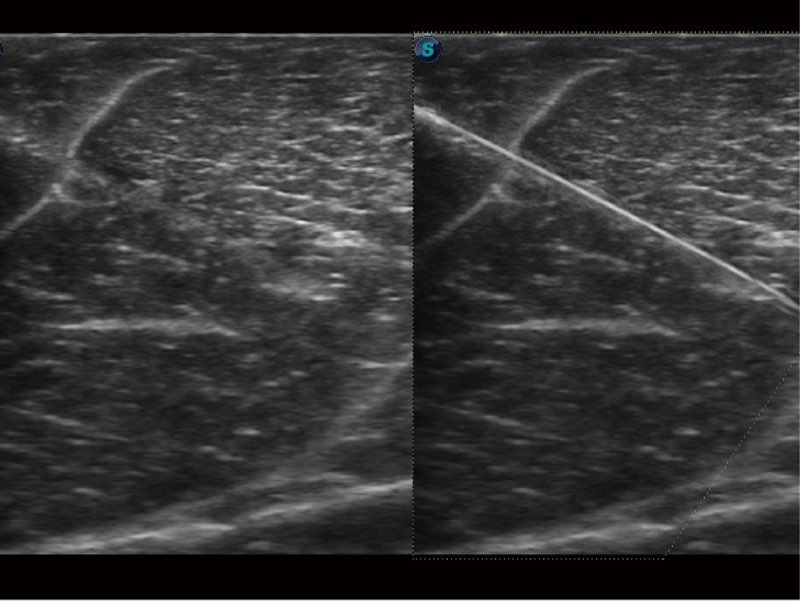

Przy pracach nad aparatem ProPet 60 uwzględniono najważniejsze preferencje i potrzeby weterynarzy, oferując finalnie przystępne cenowo i odpowiednio wyważone połączenie znakomitej precyzji klinicznej, zwiększonej wydajności i przemyślanego przebiegu pracy, niezastąpione w codziennej praktyce weterynaryjnej. Dzięki dostępowi do pełnej gamy głowic HD rozwiązanie to spełnia wszystkie potrzeby w zakresie obrazowania, umożliwiając wykonywanie badań jamy brzusznej, małych narządów, ortopedycznych, badań podczas rozrodu, a nawet badań serca i klatki piersiowej, a to wszystko przy doskonałym stosunku jakości do ceny.